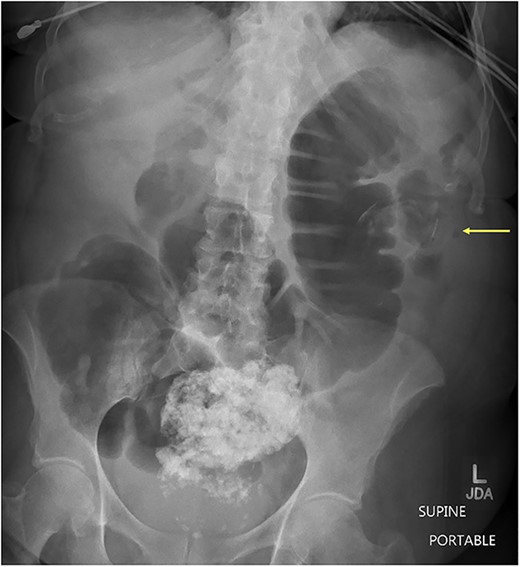

Case presentation # 1: An 80-year-old female with congestive heart failure and hypertension, presented to the emergency room with 4 days of diffuse abdominal pain associated with nausea, vomiting and anorexia. She was hemodynamically stable upon presentation, with upper abdominal tenderness on exam. Initial imaging (Figs 1 and 2) was obtained, showing a CCF with large bowel obstruction caused by an 8-cm gallstone in the descending colon. The patient was taken to the operating room for an exploratory laparotomy, where upon inspection a large gallstone in the descending colon and a fistulous communication between the gallbladder and hepatic flexure of the colon were noted. Takedown of the fistula was attempted, however because of extensive colonic involvement a decision was made to perform a right hemicolectomy with primary anastomosis, as well as a partial cholecystectomy at the level of infundibulum due to chronic inflammation and thickening of the gallbladder. The gallstone was taken out with the specimen (Fig. 3). The postoperative course was significant for exacerbation of heart failure, but ultimately, she was discharged home upon successful tolerance of a regular diet with return of bowel function.

Supine abdominal x-ray showing colonic dilation secondary to large enterolith within the descending colon. (Arrow pointing enterolith).